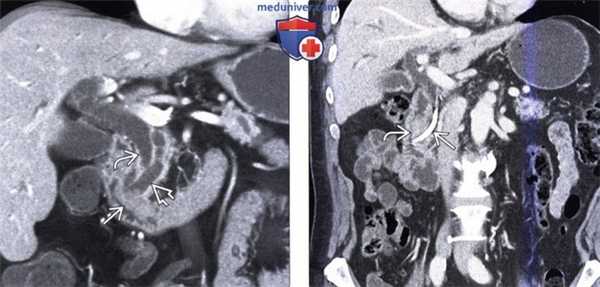

(Слева) На корональной КТ с контрастным усилением в ампуле фатерова сосочка визуализируется объемное образование округлой формы, с четкими контурами, приводящее к обструкции общего желчного протока. Рак ампулы практически всегда приводит к обструкции общего желчного протока, однако обструкция панкреатического протока возникает только в 50% случаев.

(Справа) На аксиальной КТ с контрастным усилением визуализируется инвазивная аденокарцинома ампулы фатерова сосочка, возникшая из ворсинчатой аденомы. Обратите внимание на циркулярное объемное образование большого размера (в виде «огрызка яблока») двенадцатиперстной кишки, располагающееся на границе ее второй и третьей части.